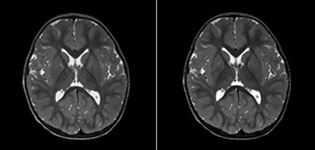

Pseudo-continuous arterial spin labeling (pCASL) was developed for brain perfusion imaging without contrast agent. “This is very desirable in pediatric patients where the general trend is to limit the administration of contrast,” says Dr. Miller. Growing confidence in specific applications “We built up confidence in pCASL by comparing it to contrast-based perfusion imaging. Once we had confidence that it was representing what the contrast perfusions were representing, we increased our diagnostic confidence by serial imaging in either the acute stage or the long term stages in a number of patients with arterial abnormalities.

Dr. Miller uses pCASL for all patients who present with chronic and acute cerebrovascular abnormalities such as acute stroke, as well as patients who present with signs of acute inflammation in the brain, and occasionally in patients with tumors, to assess the perfusion status of their tumor.

“In combination with diffusion weighted imaging, it can help give a more extended assessment of the degree of perfusion abnormality in a patient who is suffering acute ischemia. We have a number of patients who have chronic arterial insufficiency due to prior arterial abnormalities or acquired arterial abnormalities such as sickle cell disease or neurofibromatosis. Sometimes the child’s first manifestation of disease progression is a reduction in brain perfusion before stroke symptoms manifest clinically or in diffusion weighted imaging. We use pCASL to help delineate the perfusion abnormality.”

To other new users I would recommend to also start to interpret the pCASL images in comparison with other standard imaging – T2 and FLAIR and DWI – until the user gains confidence in interpreting these images by themselves.” “A powerful use of pCASL is in patients with chronic cerebrovascular stenosis, where clinicians desire information on how compensatory mechanisms of the brain are performing to enable perfusion to the brain. Often clinicians take into account how the compensatory mechanisms appear to help to provide adequate perfusion to the patient’s brain, and they may intervene surgically or make some other management decision.” “Another special application is the assessment of cerebrovascular reactivity with a Diamox perfusion exam, where we subtract two sets of pCASL images.”